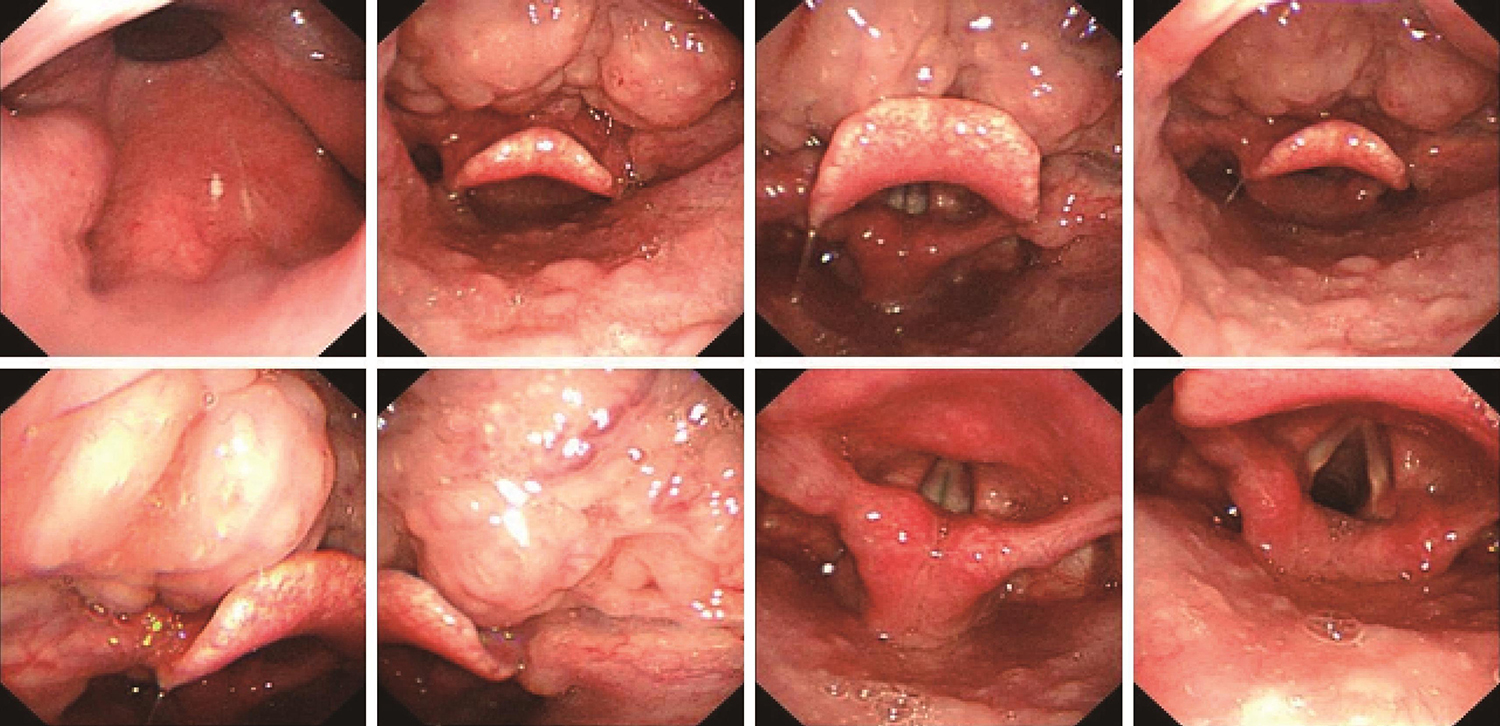

1.2011年11月29日电子喉镜检查

舌根淋巴滤泡增生,舌根部左侧增厚(图1)(性质待病理检查)。

图1电子喉镜检查示舌根淋巴滤泡增生,舌根部左侧增厚